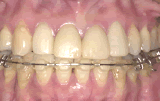

症例1/前歯が出ているのが気になる

【歯科手術中】

(器具を取り付けた状態)